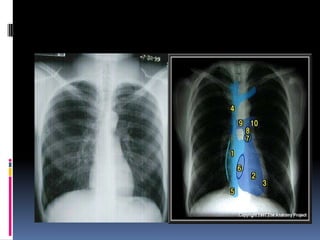

Heart

   Size

   Shape

   Silhouette-margins should be sharp

   Diameter (>1/2 thoracic diameter is

enlarged heart)

 AP views make heart appear larger than it

actually is.

Costo-phrenic / cardiophrenic angles

Margins should

be sharp

Heart  Size  Shape  Silhouette-margins should be sharp  Diameter (>1/2 thoracic diameter is enlarged heart)  AP views make heart appear larger than it actually is.

Costo-phrenic / cardiophrenicangles Margins should be sharp